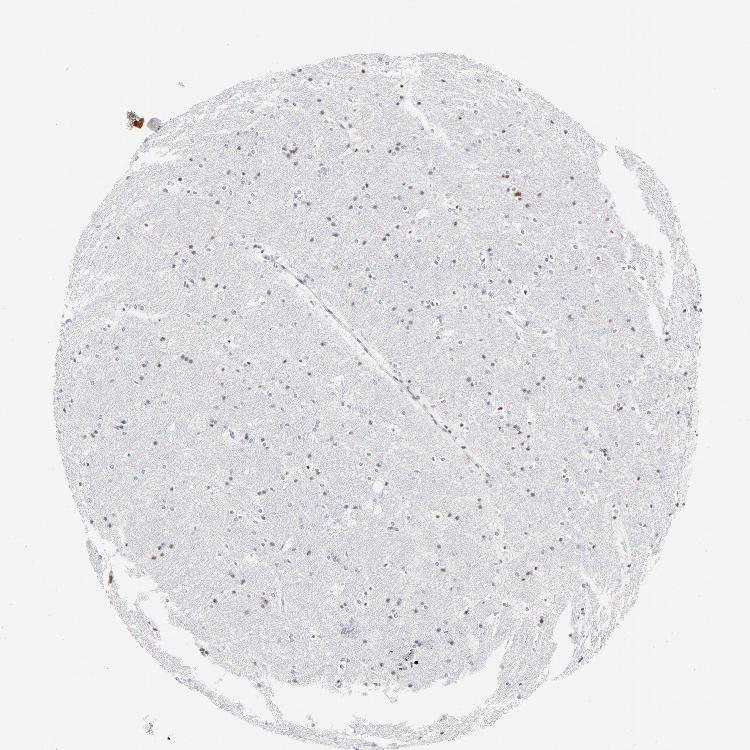

HIPPOCAMPUS - Antibody stainingi

Antibody staining in the annotated cell types in the current human tissue is reported as not detected, low, medium, or high, based on conventional immunohistochemistry profiling in selected tissues. This score is based on the combination of the staining intensity and fraction of stained cells.

Each image is clickable and will lead to virtual microscopy that enables deeper exploration of all samples and also displays staining intensity scores, fraction scores and subcellular localization as well as patient and tissue information for each sample.

Antibody HPA003402

Glial cells Not detected

Neuronal cells Low